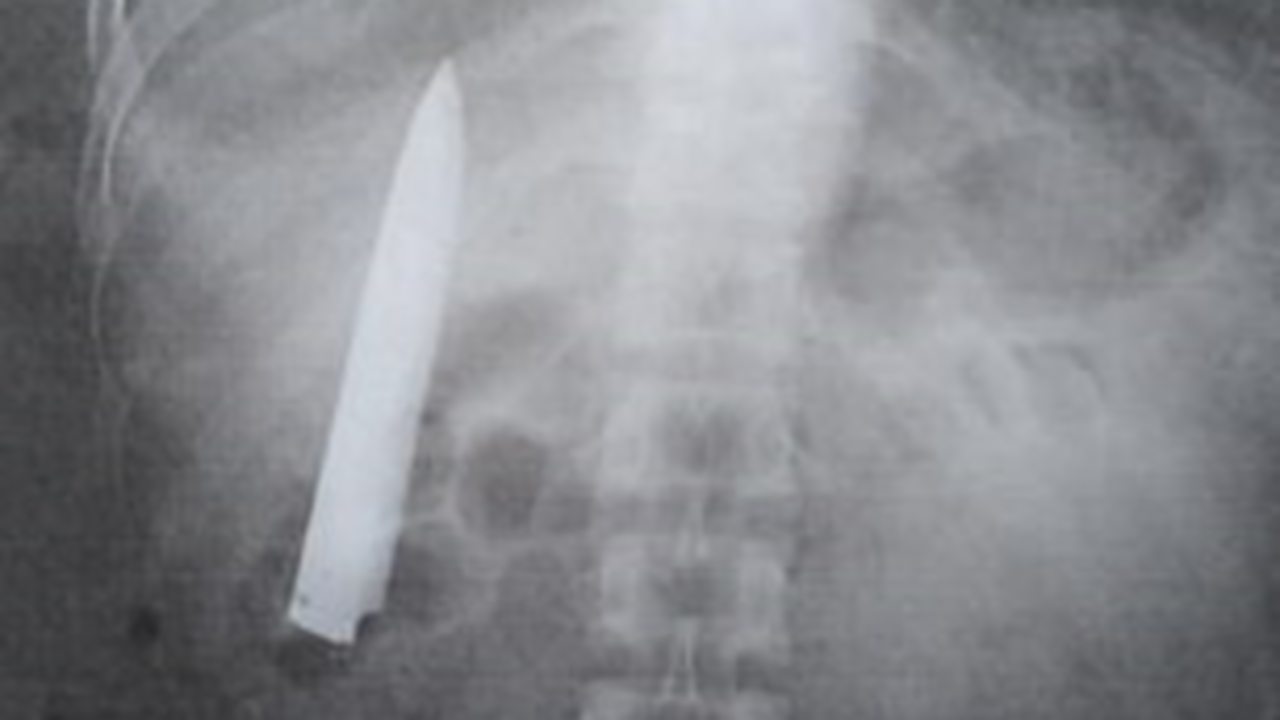

Нож В Груди Фото 114 фотографий